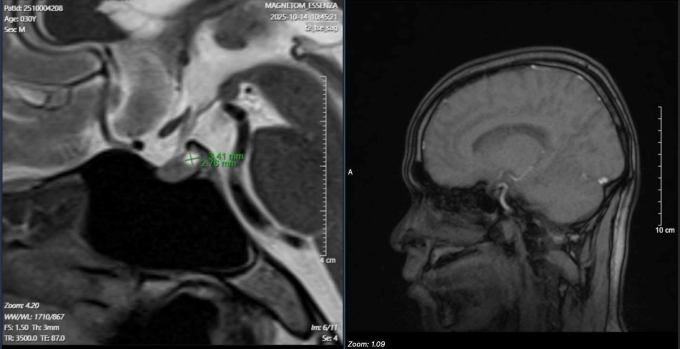

Kết quả xét nghiệm thấy nồng độ hormone prolactin trong máu tăng cao bất thường - dấu hiệu tuyến yên đang bị rối loạn hoạt động. Dựa trên kinh nghiệm lâm sàng, bác sĩ Lực tư vấn chụp MRI tuyến yên, kết quả xác nhận bệnh nhân có u tuyến yên. Khối u lành tính nằm ngay vùng não nhưng đang "khống chế" toàn bộ hệ sinh dục, gây tăng tiết hormone prolactin, ức chế trục nội tiết quan trọng, dẫn đến suy giảm ham muốn và rối loạn cương dai dẳng.

Bệnh nhân được chuyển sang khoa Phẫu thuật Thần kinh để tiếp tục điều trị khối u tuyến yên, đồng thời bổ sung testosterone ngoại sinh nhằm khôi phục lại chức năng sinh dục bị suy giảm.